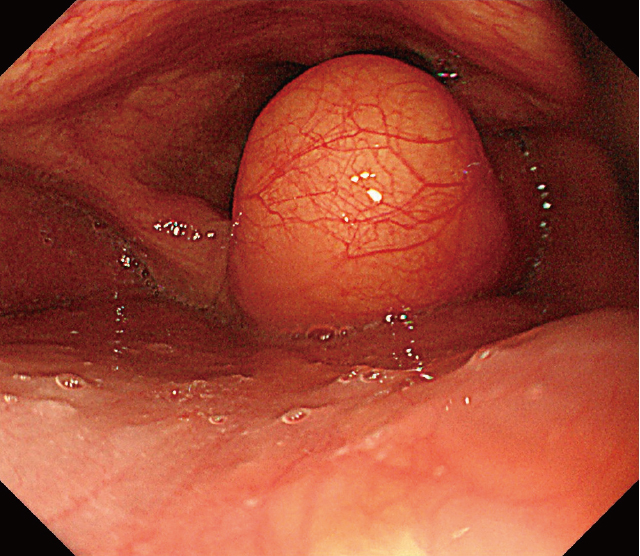

上部内視鏡検査:下咽頭右梨状陥凹に,表面平滑で黄色調の粘膜下腫瘍を認める(Figure 1).腫瘍は披裂喉頭蓋ひだに付着し,右側壁に連続しているように観察された(Figure 2).

下咽頭梨状陥凹に表面平滑,黄色調の粘膜下腫瘍様病変を認める.